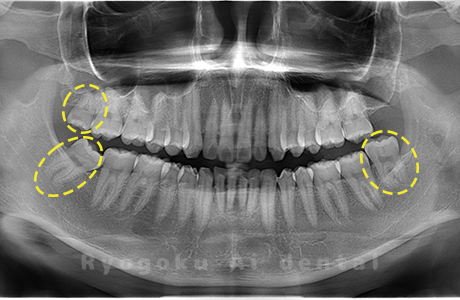

Case03

-

- 原因

- 上顎、下顎の親知らず

- 治療内容

- 上下4本の親知らずを抜歯したケースです。

<リスク・副作用>

手術後は痛み、腫れ、痺れなどの副作用が生じる場合があります。